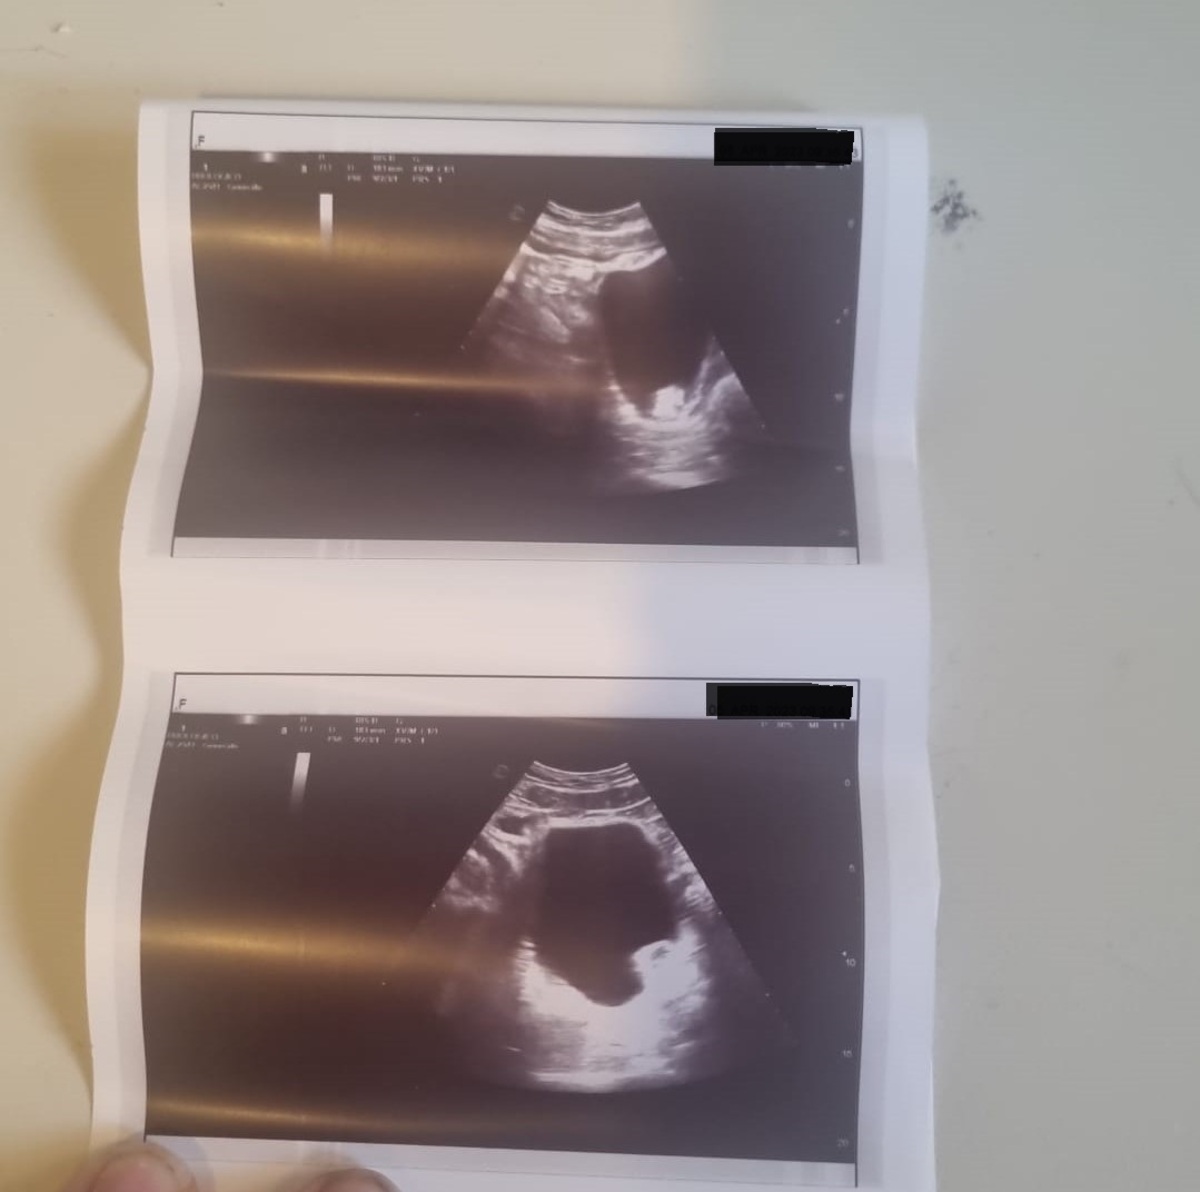

L’1 aprile il 43enne, osservando la presenza di sangue nelle urine – non era il primo episodio - si è recato al Pronto soccorso dell’ospedale San Gerardo di Monza; qui, però, gli è stata prescritta solo una visita urologica da compiersi nelle successive 72 ore, ed è stato dimesso in codice verde. Non convinti della situazione, e continuando a notare sangue nelle urine, marito e moglie si sono dunque recati a un altro Pronto soccorso, quello del Policlinico nella stessa città. Anche qui, però, nonostante venga eseguita un’ecografia all’apparato urinario, non viene evidenziato alcunchè, e l’uomo viene dimesso con codice bianco, qualche consiglio medico e la prescrizione di un controllo nei successivi 30-60 giorni.

“Sentivo che qualcosa non tornava, ero allarmata – racconta la moglie – Così ho insistito per accompagnarlo in una struttura privata”. Qui, dopo un’altra ecografia, la scoperta: sospetta neoplasia (massa tumorale) alla vescica di quasi 3 cm, con richiesta di effettuare urgentemente una biopsia.